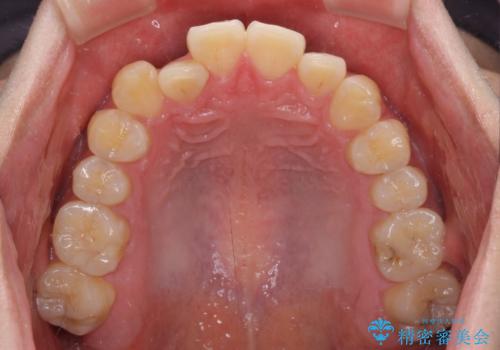

八重歯と前歯のクロスバイト ワイヤー装置で短期間矯正

- 八重歯を気にして来院された患者様です。

上顎側切歯(前から2番目の歯)が内側に転位している歯列は、インビザラインでは排列が困難であることが多いため、期間を短く、より良い仕上がりとするため、ワイヤー装置にて矯正治療を行うこととしました。